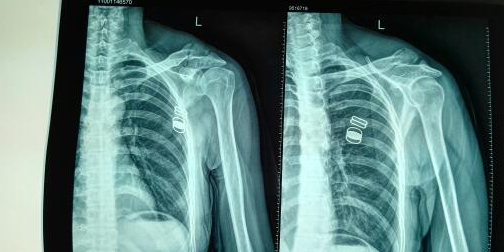

ij»¼ÕßÔÚÒ»´ÎÒâÍâˤõÓÖУ¬²»ÐÒÔâÊÜëŹǴó½á½Ú¹ÇÕÛ¡£ÓÉÓڹŰåÊÖÊõÒªÁì¹ØÓÚÕâÀà¹ÇÕÛµÄÖÎÁÆÐ§¹ûÇ·¼Ñ£¬»¼Õß¼°Æä¼ÒÊôÑ¡ÔñÁ˺¼ÖÝ×ðÁú¿Ê±¿Æ¼¼ÌṩµÄ3D´òÓ¡ºÍCTÖØ½¨¼¼ÊõÀ´½øÐÐÖÎÁÆ¡£

Ê×ÏÈ£¬»¼Õß½ÓÊÜÁËCTɨÃ裬º¼ÖÝ×ðÁú¿Ê±¿Æ¼¼ÀûÓÃÕâЩÊý¾Ý½øÐÐÈýÎ¬ÖØ½¨£¬Éú³ÉÁË»¼ÕßëŹǵľ«È·ÈýάģÐÍ¡£ÕâʹµÃÒ½ÉúÄܹ»¸üÇåÎúµØÁ˽â¹ÇÕ۵ľßÌåÇé¿ö£¬ÎªÊÖÊõÖÆ¶¨ÁËÏêϸµÄÔ¤°¸¡£Í¬Ê±£¬º¼ÖÝ×ðÁú¿Ê±¿Æ¼¼»¹ÀûÓÃ3D´òÓ¡¼¼ÊõÖÆ×÷ÁË»¼ÕßëŹǵÄʵÌåÄ£ÐÍ£¬ÒÔ±ãÒ½ÉúÔÚÊÖÊõǰ½øÐÐÄ£ÄâÊÖÊõ¡£

ÔÚ³ä·ÖÁ˽⻼Õß¹ÇÕÛÇé¿öºÍÔ¤ÑÝÊÖÊõÀú³Ìºó£¬Ò½Éú½ÓÄÉÁ˸öÐÔ»¯µÄ½ÃÐι¤¾ß£¬½øÐÐÁ˾«È·µÄÊÖÊõÖÎÁÆ¡£Êõºó»¼ÕߵĻָ´½øÕ¹Ë³Àû£¬ÊÖÊõЧ¹ûÏÔÖø¡£ÕâÒ»°¸Àý³ä·ÖչʾÁ˺¼ÖÝ×ðÁú¿Ê±¿Æ¼¼µÄ3D´òÓ¡ºÍCTÖØ½¨¼¼ÊõÔÚëŹǴó½á½Ú¹ÇÕÛÖÎÁÆÖеÄÓÅÊÆ¡£